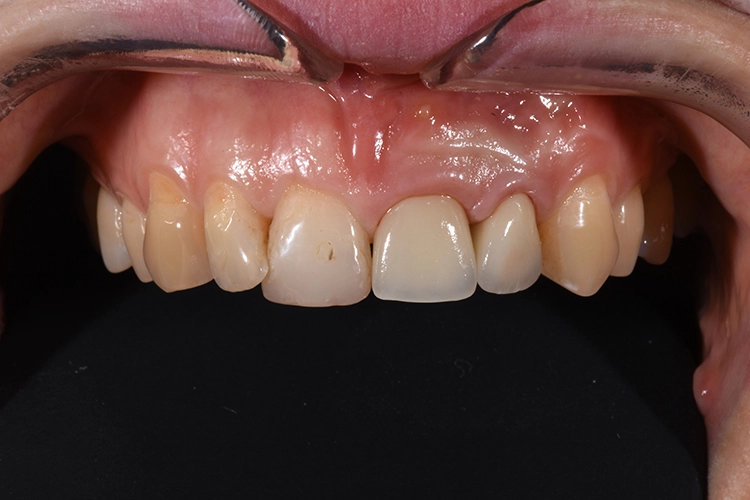

Fall 3: Sofortimplantation

Dr. Blume

Zu unserem Ausgangsbefund zählt die sechs Punkt-Taschenmessung, die Vitalität und Perkussionsprobe sowie ein Röntgenbild. Besonders wichtig ist in diesem Zusammenhang auch die genaue Anamnese des Patienten.

Deutlich auffallend und für die Patientin sehr wichtig war die anatomisch individuelle Zahnstellung des Zahnes 11. Um dem Wunsch der Patientin auf eine für ihr Umfeld unauffällige Behandlung gerecht zu werden, entschieden wir uns gemeinsam für eine Sofortimplantation mit einer provisorischen Sofortversorgung des Implantates. Kein Provisorium kommt der Natur so nah wie die Natur selbst und daher planten wir die Umarbeitung der Zahnkrone 11.